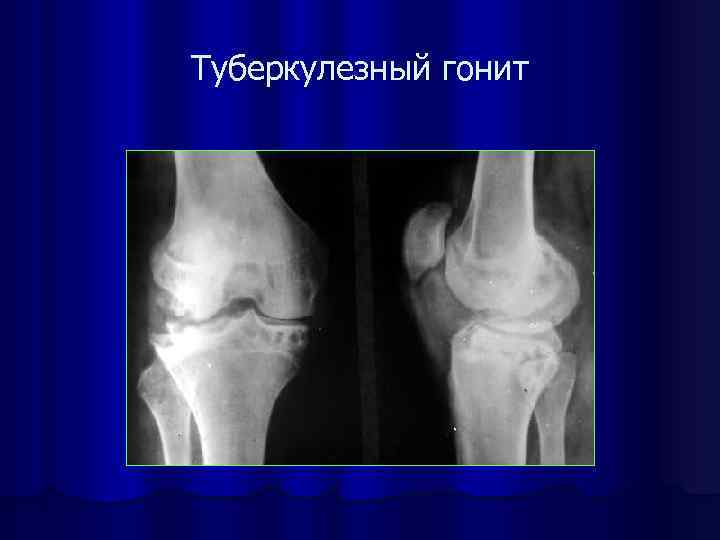

Туберкулезный гонит